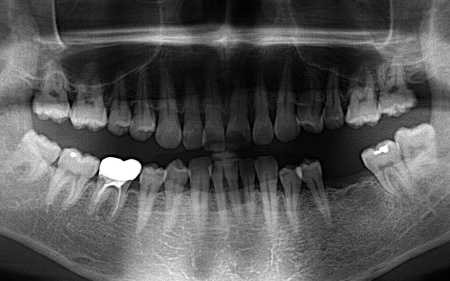

そこで、まずはレントゲンやCTによる検査を実施しました。

その結果、十分な骨の量があり、噛み合わせの歯もインプラントを入れた際に自然に噛める位置に生えていたため、インプラント治療を行う条件は問題ないと判断しました。

拝見したところ、左下奥歯(第1大臼歯)が抜けており、見た目が気になるだけでなく奥歯でしっかりと噛むことが難しくなっていました。

また、安定したインプラント治療を行うためにはインプラントを支えられるあごの骨が残っているか、インプラントの上に人工歯を取り付けた際に噛み合わせの歯が邪魔をしないかなどを確認する必要があります。